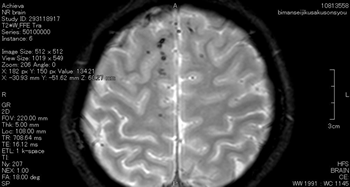

症状固定段階でのT2スター強調のMRI画像です。頭頂部から頭蓋底に至る24枚のMRI画像の内の6枚目の画像です。

前頭葉、両側頭葉に黒い点がいくつか映っています。これは、脳表面の広範囲に広がる点状出血が画像として映ったものです。びまん性軸索損傷があることを示します。

点状出血を矢印で示したものが下の画像です。

被害者はフルフェイスのヘルメットを装用していました。頭蓋骨骨折や脳挫傷はありませんでした。

しかし、広範囲の点状出血に伴う軸索の損傷があります。失語、記憶、聴覚や嗅覚、言語理解、認知の領域で、脳は大部分の機能を喪失してしまいました。